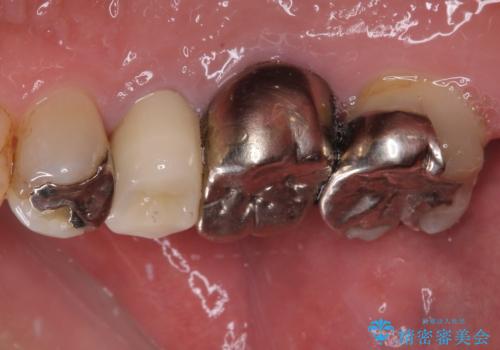

もげてしまった奥歯 オールセラミッククラウンでの補綴治療

- 食事中に歯がもげてしまったとのことで来院された患者様です。

レントゲン写真から、特に大きなむし歯などは認められませんでしたが、根管治療があまり十分に行われているとは言えない状態でした。

まずは仮歯を装着し、根管治療を行った上で土台を植立し、オールセラミッククラウンにて補綴治療を行うこととしました。

反対咬合で奥歯に負担のかかる咬み合わせのため、就寝時に強い力がかからないよう、マウスピースを装着していただくよう指示をしました。